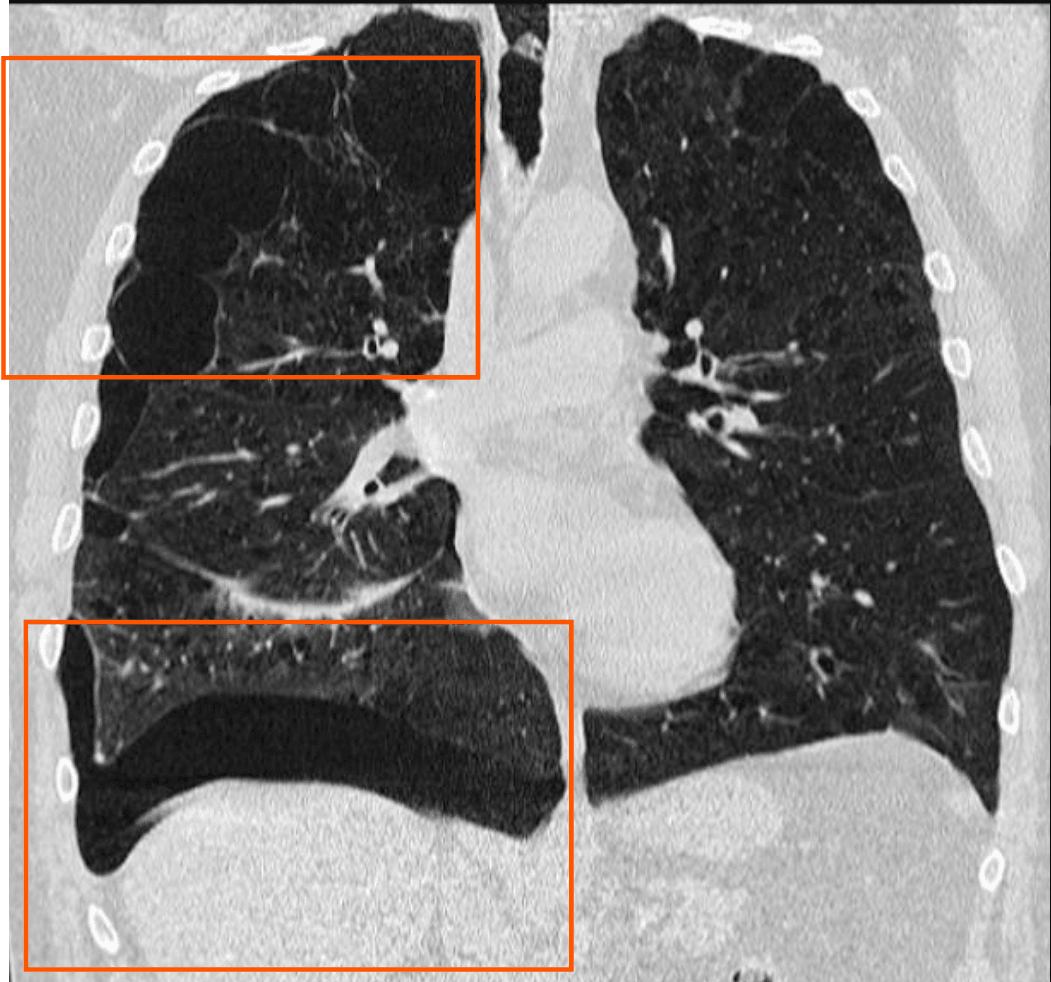

CT 소견

작은 기흉까지 감별 가능하며, 폐포 손상 및 기도 이상을 보다 정밀하게 평가.

| CT 소견 |

| 🔵 공기 음영 증가: 흉막강 내 공기가 명확하게 보이며, 폐 실질과 구분됨. |

| 🔵 늑막 두께 변화: 기흉으로 인해 내측 흉막과 외측 흉막 사이 간격이 증가. |

| 🔵 종격동 변위: 긴장성 기흉의 경우 압력 증가로 인해 심장 및 기관이 반대쪽으로 밀려남. |

Cuete D, Secondary spontaneous pneumothorax.

영상 소견상 특징

- Right Pneumothorax

- Signs of bullous emphysema of apical predominance